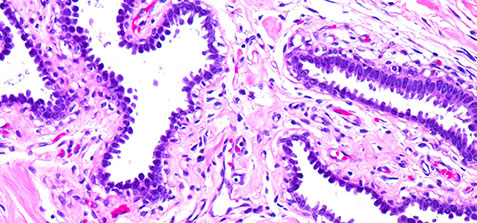

Our electronic medical records (EMR) system is available to you through a secure web portal so you can download reports with full color microphotoscopy in PDF format at any time. We can work with you to fully integrate our EMR system with yours for even more convenience and accessibility. In addition, we can deliver reports via postal service, email, fax, and courier.

Example Reports